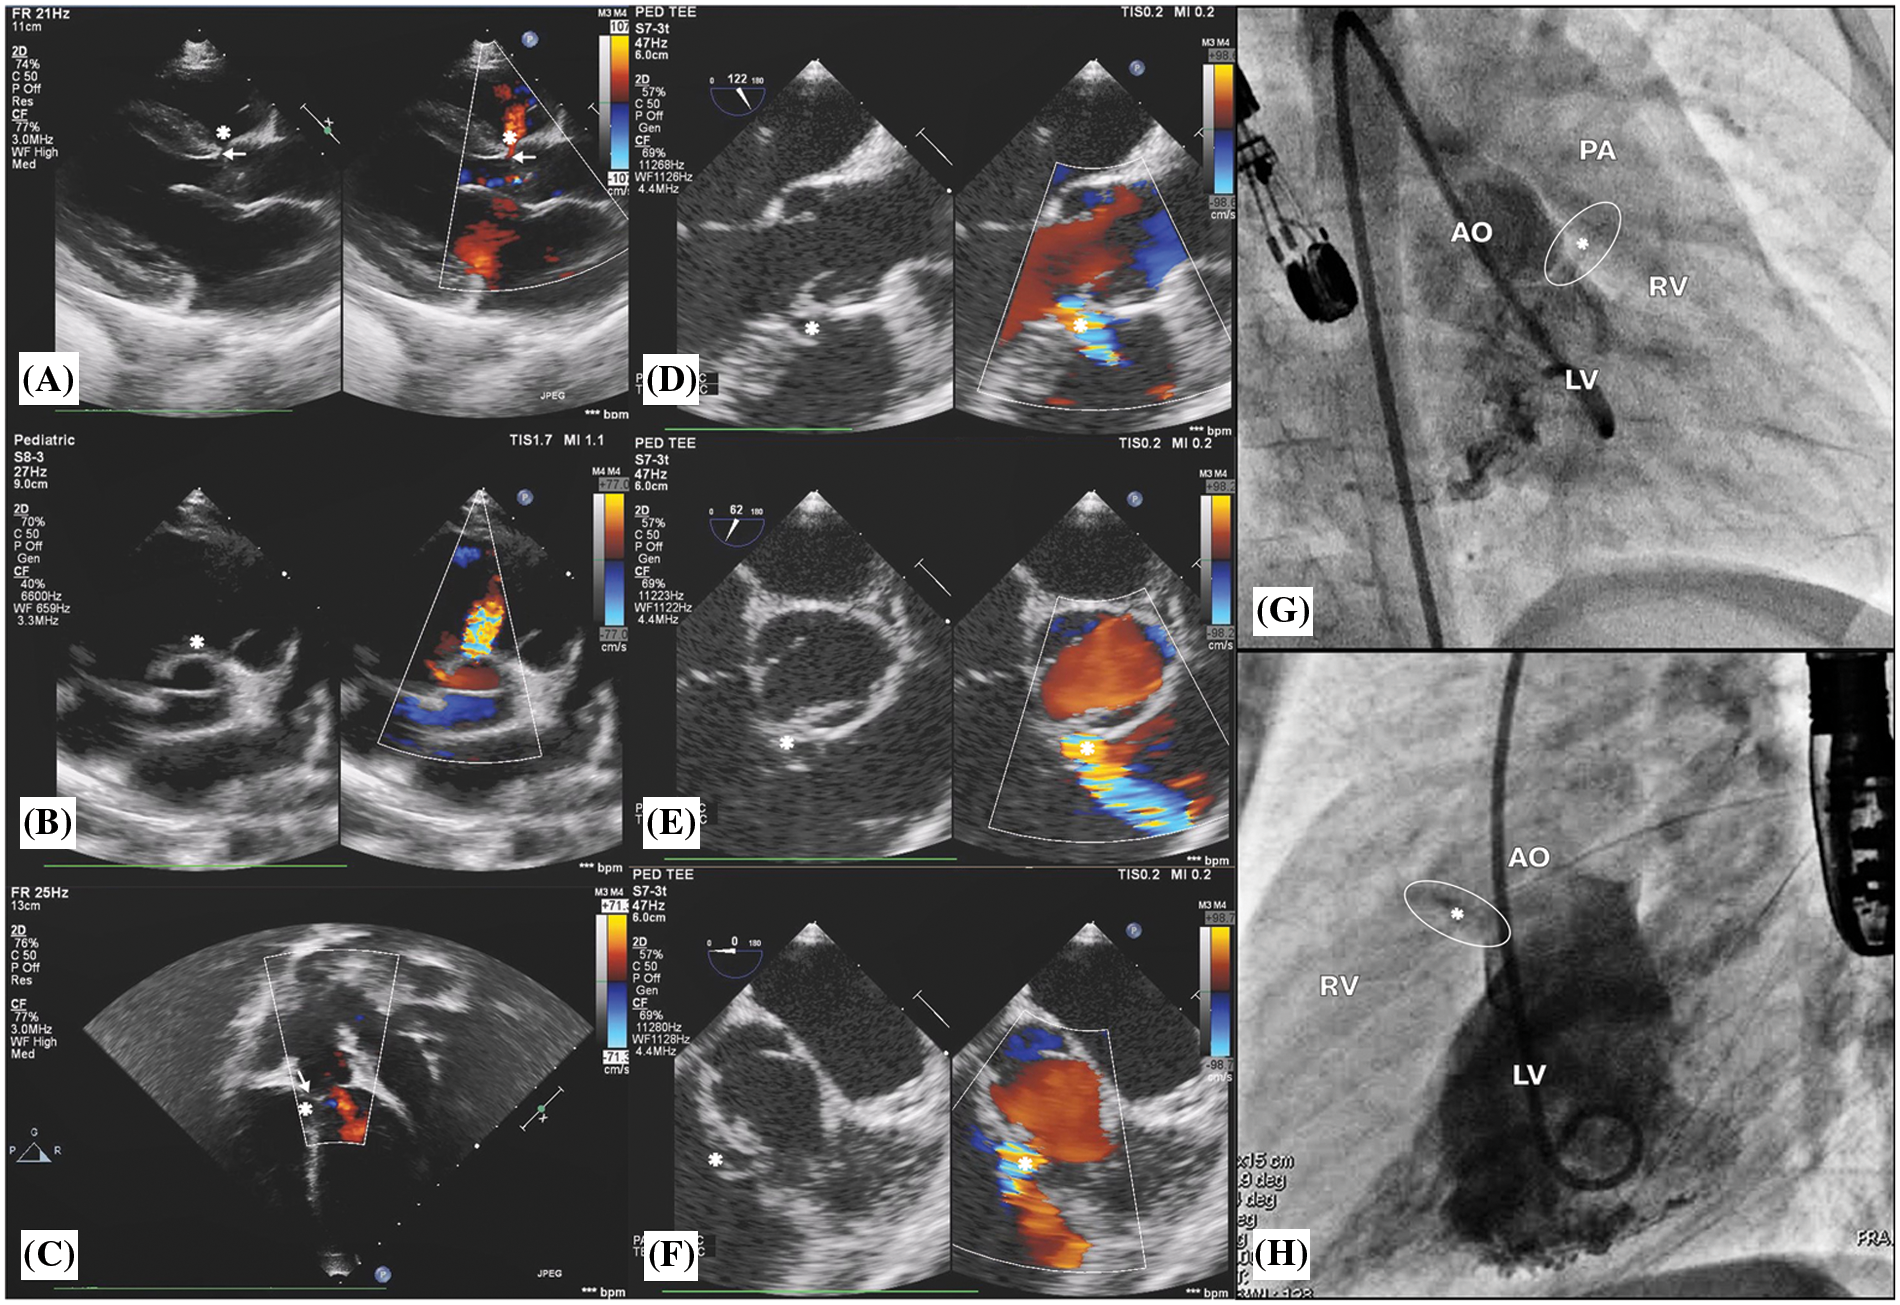

The OVSD was diagnosed by demonstrating the dropout of the interventricular septum with aortic-pulmonic valve fibrous continuity and the presence of a colour flow jet around the 12–2 o’clock position in the parasternal short-axis view of TTE [4] or around the 6–8 o’clock position in the short-axis with the mid-oesophageal view (40°–60° rotation) of TOE [5]. In addition, from the cardiac catheterization, the left-to-right shunt underneath the aortic and the pulmonary valves pointing up toward the right ventricular outflow tract (RVOT) from the left ventriculogram in the right anterior oblique (RAO) and true lateral projections confirmed the diagnosis of OVSD (Fig. 1). The VSD diameters and length from echocardiogram were the average of the measurements in 2 orthogonal image planes whilst from left ventricular (LV) angiogram were the most visualized numbers in lateral and/or RAO projections during systole. Nonetheless, for those with aortic valve prolapse, repeated angiogram may require after passing the delivery sheath to interrogate the true defect diameter after pushing the aortic cusp away. The largest right ventricular (RV) orifice diameter will be used for device size selection.

Figure 1: Transthoracic echocardiogram findings: (A), (B), and (C) show outlet ventricular septal defect, OVSD (*) and aortic valve prolapse (arrow) with mild AR. Transoesophageal echocardiogram findings: (D), (E), and (F) show OVSD (*) in the 120°, 60°, and 0° of the mid-oesophageal view. Left ventricle (LV) angiogram findings: (G) and (H) show a contrast jet beneath the aortic valve (AO) from the LV to the right ventricle (RV) in right anterior oblique 30° and true lateral views, respectively